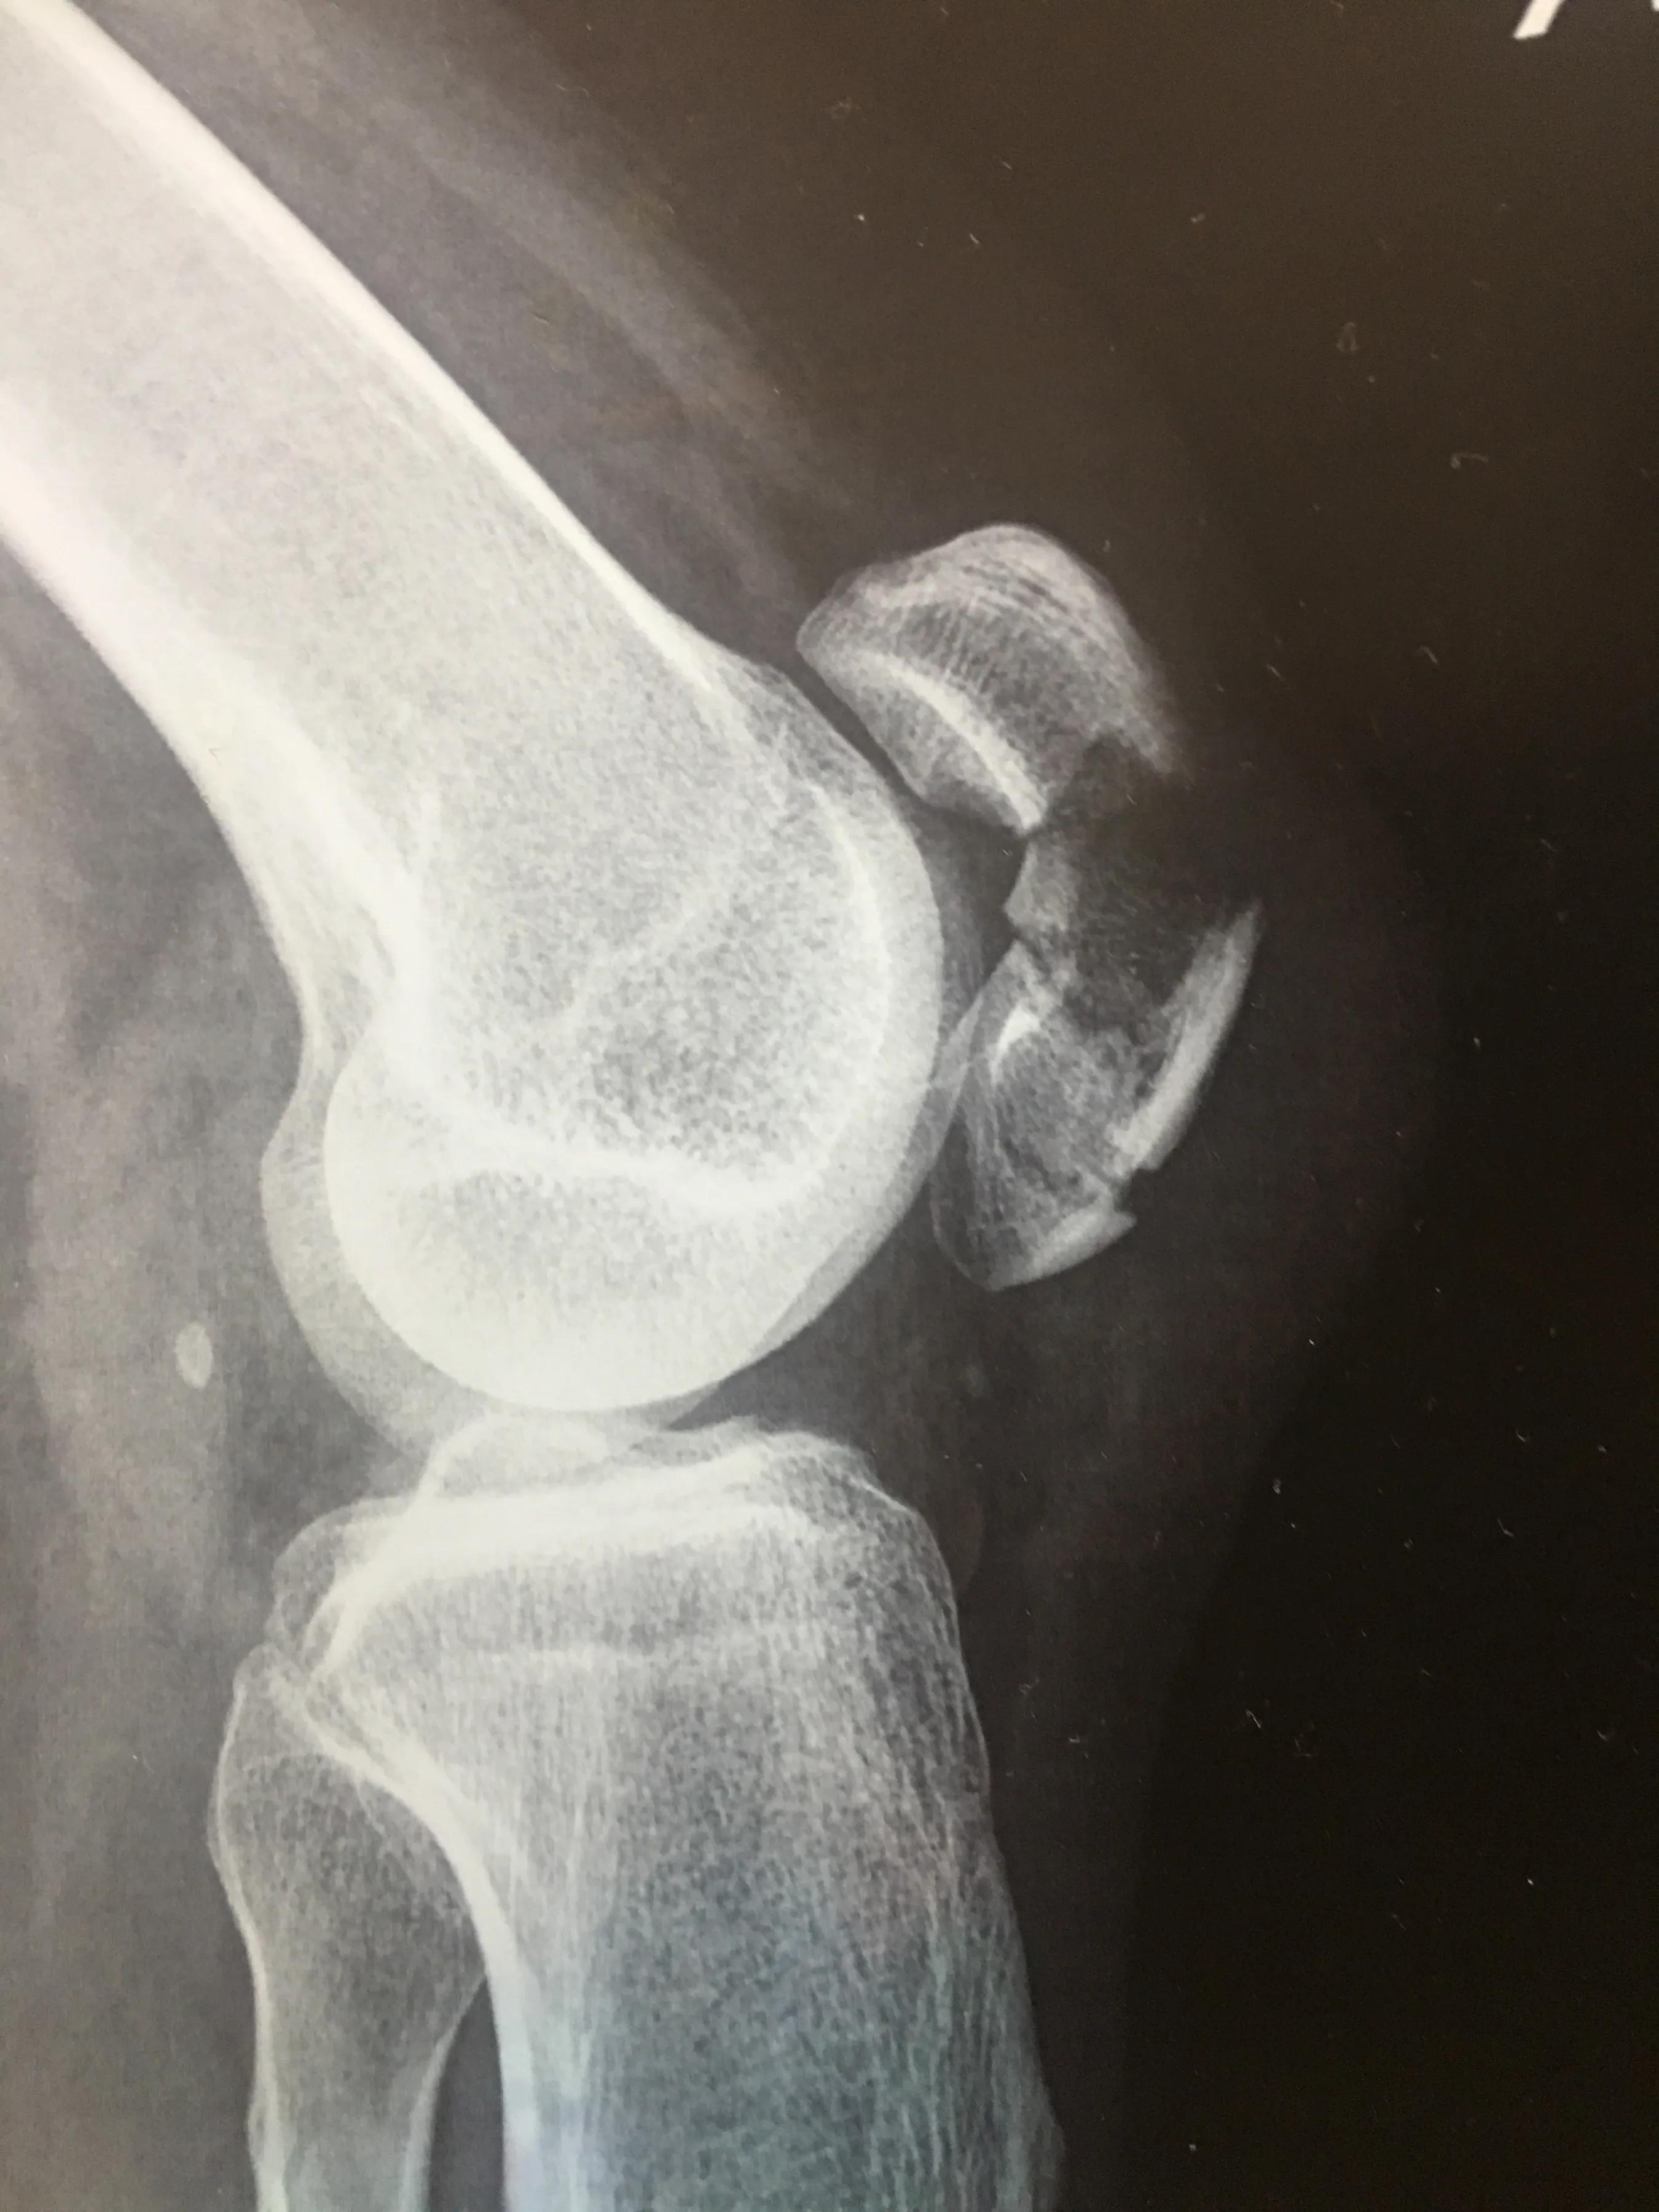

有句老话说的好“意外无处不在”,这句话真没错,本人于6月25日端午节当天,下电动车时拌了一下,右膝撞地,造成髌骨粉碎骨折。当时髌骨部位撞出一个坑,开始以为只是髌骨错位,后来到医院挂的急诊,拍片,拍的片还没出来,负责拍片的医生说,比较严重,需要手术。等片子出来后,找的骨科主治医生,医生说,办手续,住院吧!当时就懵了,感觉一切都来的太突然了,就像做梦一样。后来问了一下后续治疗过程和费用,医生说先住院消肿,大概十天左右,然后手术,术后观察几天,然后出院就行了,费用大概4万,居民医保报一半。当时因为公司有急事,实在走不开,就和医生商量能不能回家消肿,医生同意了。后来我其他亲属来了,说今天还不晚,还是去骨科医院看一下吧!医生给开了一些止痛药,加上拍片等其他费用,大概花了1千左右。

然后下午我们又赶到昆明九二零医院,挂完急诊,直接去的住院楼骨科病区,看完片子,医生说需要手术,但是现在医院没病床,先给你装一个腿下护板,回家消肿,不用吃药,因为吃不吃都是那么些天,有病床了,通知你再来。又问了一下费用,说大概一万多,报完后自费几千。当天护板费用300左右,然后就回家了。也就是从今天上护板开始,小腿就没打过弯。在家消肿前几天,膝盖肿的厉害,疼痛感不是很强烈,后来吃了大概有一瓶云南白药胶囊32粒装,明显感觉不痛了,肿也消得很快。消肿这几天,在家拄拐活动。过了大概七八天时,医生打电话,但我没接到,后来打回去才知道,病床又没有了,还得等。大概等到7月10号,来电话说来住院吧,先住胸外科,不能再等了,再等就残废了,吓得我赶紧赶到医院,当天办的住院。又开了6张需要检查的单子,这些检查有的要预约,有的排队,等全部做完,竟然用了两天的时间,又赶上周一的手术排满了,只能14号做手术。从受伤当天到做手术,中间间隔了有18天。其实这个时间有点过长,对后期恢复关节活动有一些影响的。做完手术后第四天办的出院,术后的第二天就要下地活动了,当时膝盖因为有伤口,还不能打弯,护板拆除。住院费用是一万三千多,自费不到七千。截止到今天,这次意外交给医院的总费用大概8千左右。其他花销比如吃的,用的,交通等,没算进去。